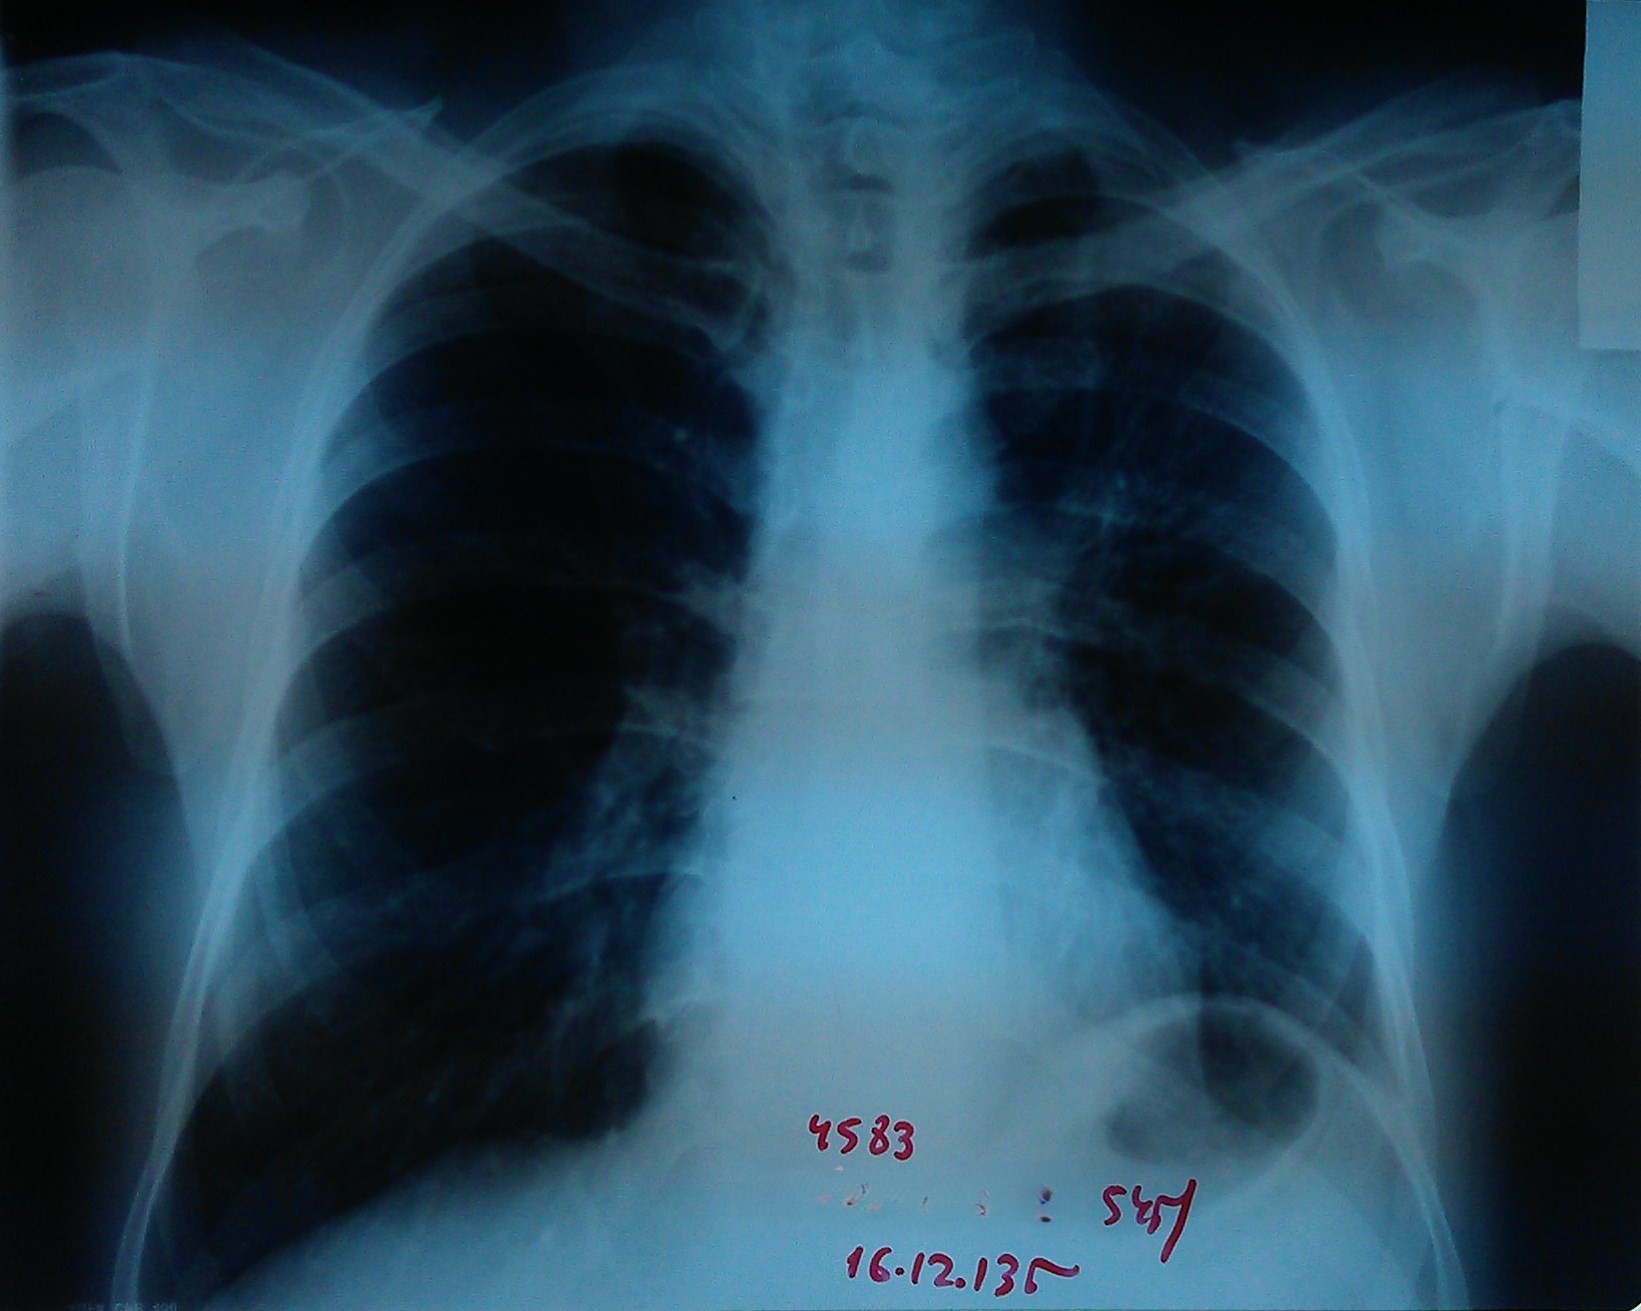

- გულმკერდის რენტგენოგრაფია რეზექციამდე 1 კვირით ადრე

სიმსივნური წარმონაქმნი მარცხენა მთავარ ბრონქში.

აღინიშნება მარცხენა ფილტვის თითქმის სრული ატელექტაზი.